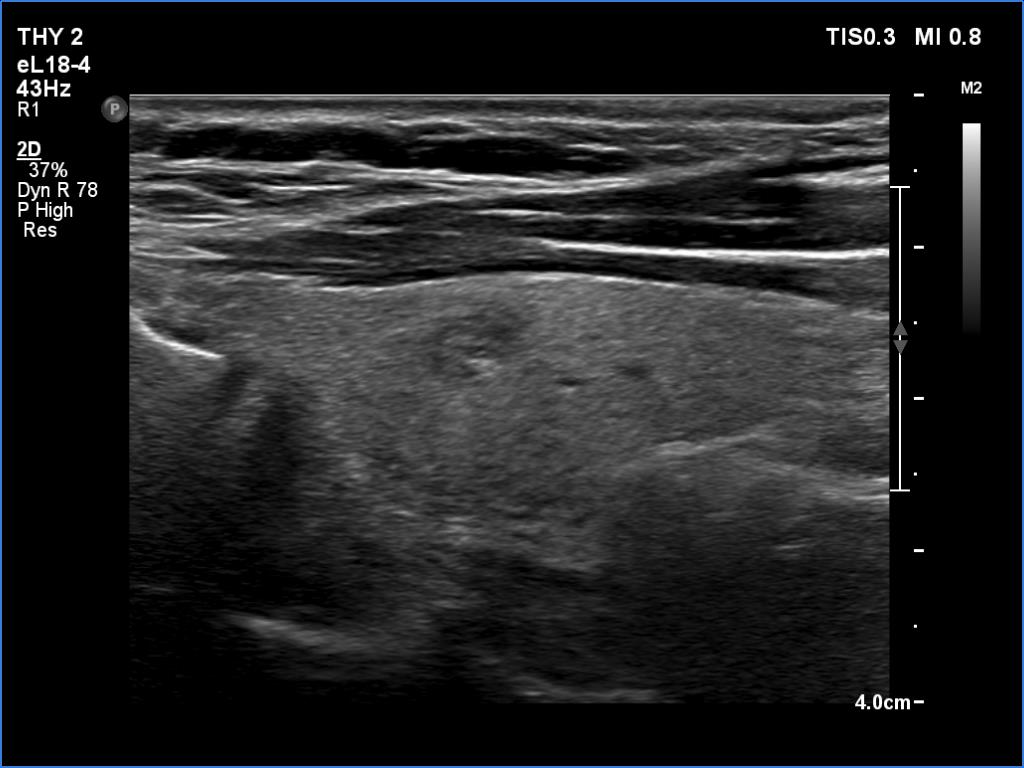

Right lobe, longitudinal scan

Right lobe, longitudinal scan. This lesion has no clinical or oncological significance.